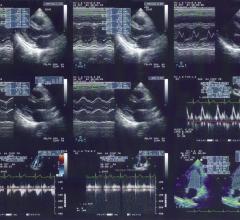

Ultrasound uses sound waves to create images. This section includes breast ultrasound, echocardiography (echo), transthoracic echo (TTE), transesophageal echo (TEE), echo contrast, transducers, ultrasound software and point-of-care ultrasound (POCUS).

November 7, 2011 — This year’s annual meeting of the European Association of Echocardiography (EAE), a registered branch ...